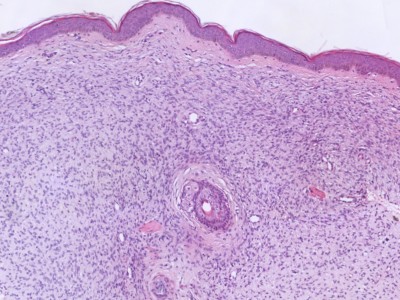

In de dermis, deels in bundels dicht opeengepakte fusiforme fibroblasten met licht vergrote, onregelmatige rond/ovale kernen, gerangschikt in een storiform patroon. Kern-atypie en (geringe) mitose activiteit. C34 positief. Er is meestal focaal veel ijzerpigment aanwezig. Naar de diepte is er uitbreiding in het vetweefsel. Zie ook de ingescande PA-coupe van de afdeling pathologie van de University of Toronto.